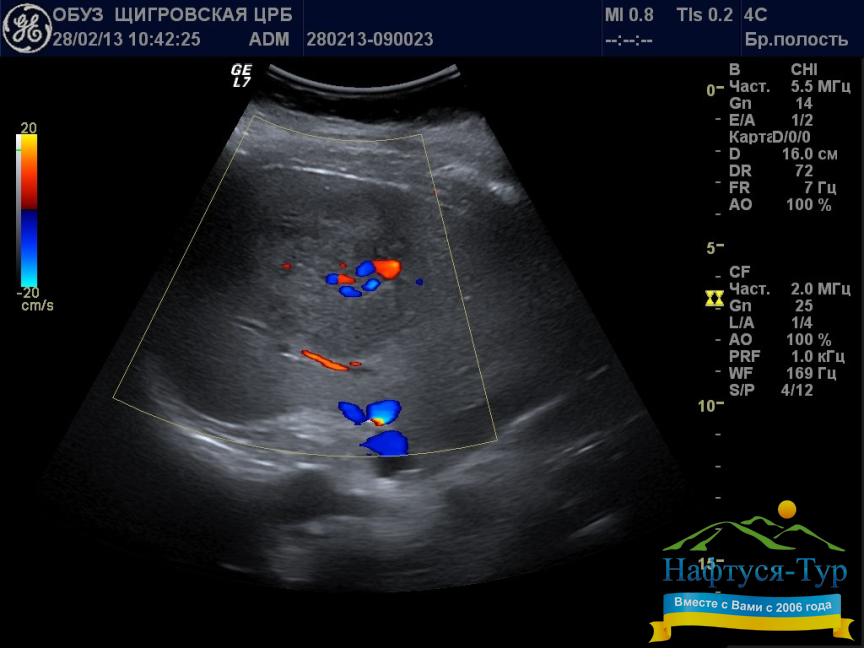

УЗИ (Ультразвуковое исследование) на сегодняшний день выступает одним из главных средств при диагностике чрезвычайно широкого спектра заболеваний. Соответственно, кабинет УЗИ имеется в любом санатории Украины, различия между здравницами в этом смысле могут состоять лишь в уровне используемой аппаратуры. Например, ряд современных аппаратов позволяют создавать 3D или 4D изображения внутренних органов, что резко повышает качество диагностики. К безусловным преимуществам УЗИ относятся неинвазивность, скорость, полная наглядность получаемых результатов и многие другие. Эти преимущества, в свою очередь, позволяют многократно и с высокой эффективностью использовать УЗИ на этапе первичной диагностики, а также в ходе проведения курса лечения для определения результатов, достигаемых на каждом этапе.